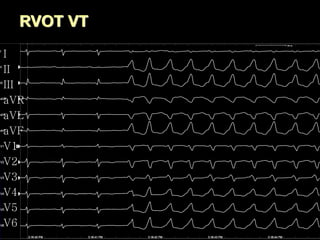

RVOT VT

I

II

III

aVR

aVL

aVF

V1

V2

V3

V4

V5

V6

Idiopathic RVOT-T

Right ventricular outflow tract tachycardia

(RVOT-T) represents up to 10% of all ventricular

tachycardias (VTs), and is considered as a

benign disease.

Symptoms: Ranging from none to palpitations,

lightheadedness, dyspnea, or syncope.

Arrhythmias: Frequent isolated PVCs, bursts of

nonsustained VT, or sustained tachycardia often

facilitated by catecholamines or exercise.

Ablation: Acute success rate of focal ablation of

RVOT-T is 65–97% with rare complications.